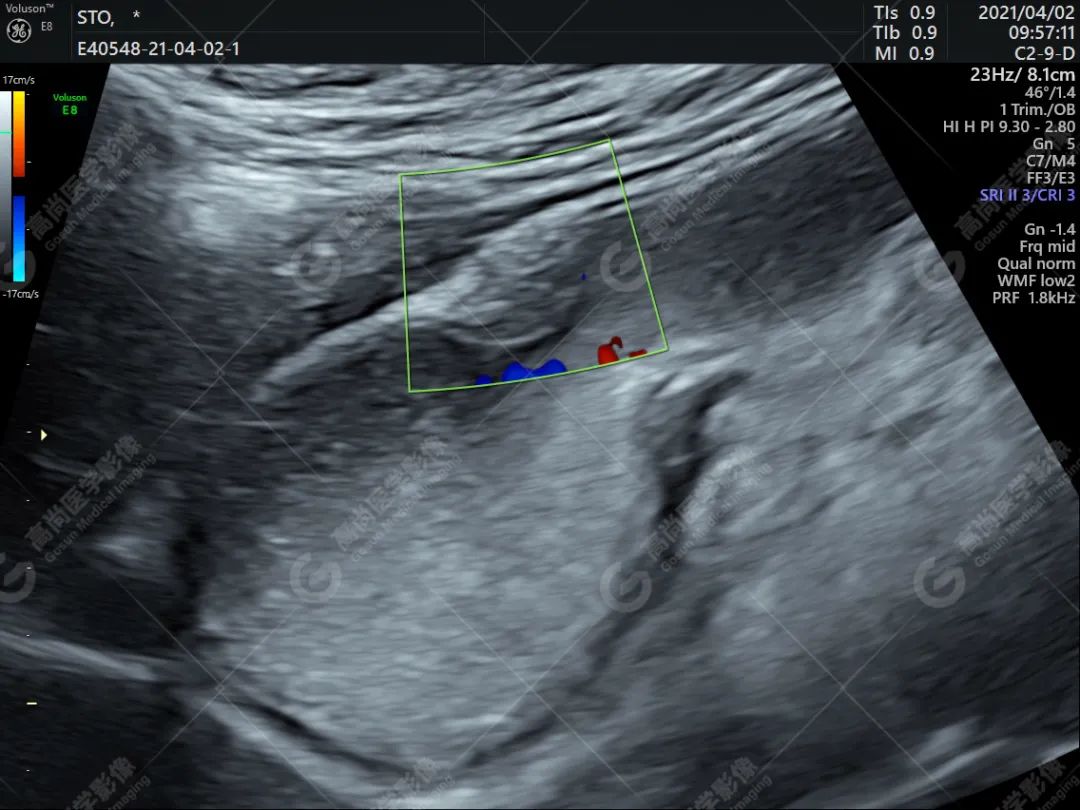

胃窦部大弯侧探及一实性低回声,大小约 9 mm×8 mm,起自粘膜层向胃腔内隆起,表面尚光滑,随胃蠕动而移动但不消失。

2. 多起源于粘膜下层,其次为肌层,也可见于粘膜层和浆膜层。呈片状中等回声,局部放大可见网格状改变,类似胰腺回声。

3. 可伴有无回声的类导管样结构。

超声能显示异位胰腺组织在胃壁内的部位、形态、大小、内部回声特征,弥补了胃镜和 X 线不能发现粘膜下小肿物的缺陷。超声检查能发现无症状的胃壁胰腺异位症,使之得到早期治疗。